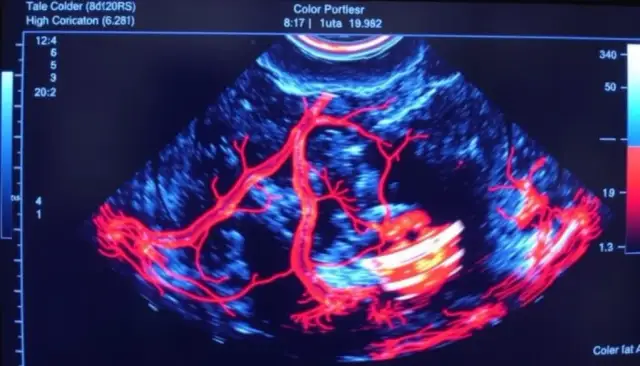

BadaniaUSG Doppler: Bezbolesne badanie przepływu krwi. Jak działa?Angelika Pawłowska-29 września 2025